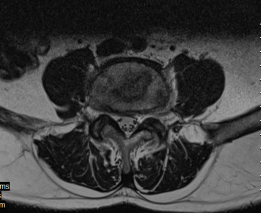

На МРТ в телах VL4-5 сигнал неоднородно снижен. Межтеловая щель сужена. Суставные поверхности неровные с узурацией, с краевыми остеофитами. Мягкие ткани вокруг инфильтрированы, утолщены, абсцессов нет. Спинномозговой канал сужен. За счет протрузии дисков VL4-5, VL5-S1 позвонков. Повышенный сигнал от тел остальных поясничных позвонков.

Рис. 1. МРТ до операции лазерной вапоризации межпозвонкового диска VL4-5

Рис. 2. МРТ при поступлении

Рис. 3. МРТ после 20 дней терапии Левофлоксацином